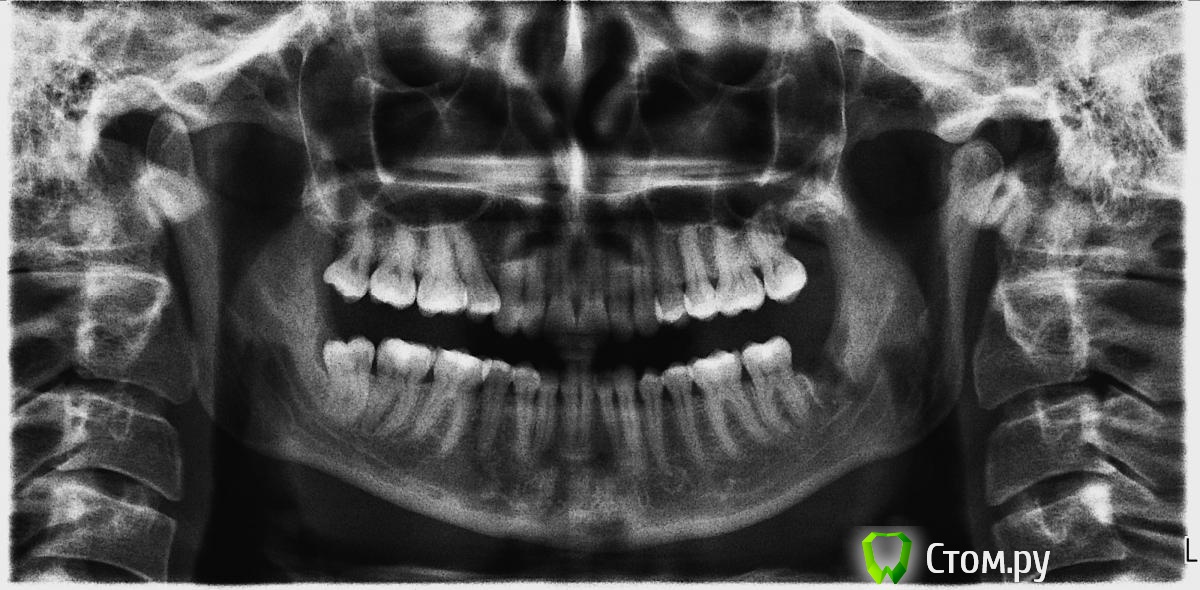

red_butler Опубликовано 12 апреля, 2014 Поделиться Опубликовано 12 апреля, 2014 (изменено) 1. Зуб сложным не выглядит, но это только плоский снимок, действительность иногда иная. Если с учётом анестезии, то бывает и более часа2. Резинка называется дренаж, иногда используется3. Бывает, перед травматичными вмешательствами4. При адекватной анестезии, боли быть не должно, но бывают исключения. Было больно, или очень неприятно?Как вариант дальнейшие вмешательства проводить под седацией Изменено 12 апреля, 2014 пользователем red_butler Ссылка на комментарий

rivezico Опубликовано 16 апреля, 2014 Поделиться Опубликовано 16 апреля, 2014 по снимку легкий, но на деле может быть сложным Ссылка на комментарий

Цунами Опубликовано 16 апреля, 2014 Автор Поделиться Опубликовано 16 апреля, 2014 (изменено) Добрый день.Сегодня сделала снимок (снимок не распечатывали на плёнке, прислали на почту, надеюсь, качество снимка хорошее?)Всё ли хорошо на снимке. Какая-то полосочка видна ближе к семёрке? Может это нитки видны?Удаление зуба было в пятницу 11 апреля. В понедельник ходила на осмотр - убрали резиночку-дренаж. Изменено 16 апреля, 2014 пользователем Цунами Ссылка на комментарий

red_butler Опубликовано 16 апреля, 2014 Поделиться Опубликовано 16 апреля, 2014 Добрый день.Сегодня сделала снимок (снимок не распечатывали на плёнке, прислали на почту, надеюсь, качество снимка хорошее?)Всё ли хорошо на снимке.Все хорошо Ссылка на комментарий